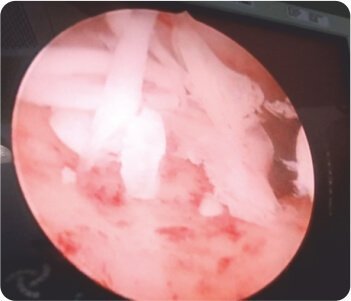

Removed bone fragments